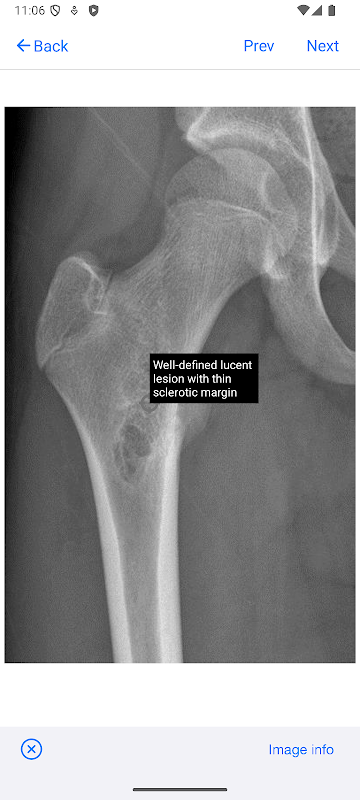

BoSTT يجلب للمستخدم تجربة حقيقية من الحالات المتكررة والنادرة، نموذجية وأكثر غرابة من العظام والأورام الأنسجة اللينة. كل حالة لها تاريخ السريري، وارتفاع القرار الأشعة وعلم الأمراض الصور والتشخيص والعلاج ونقاط التعلم.